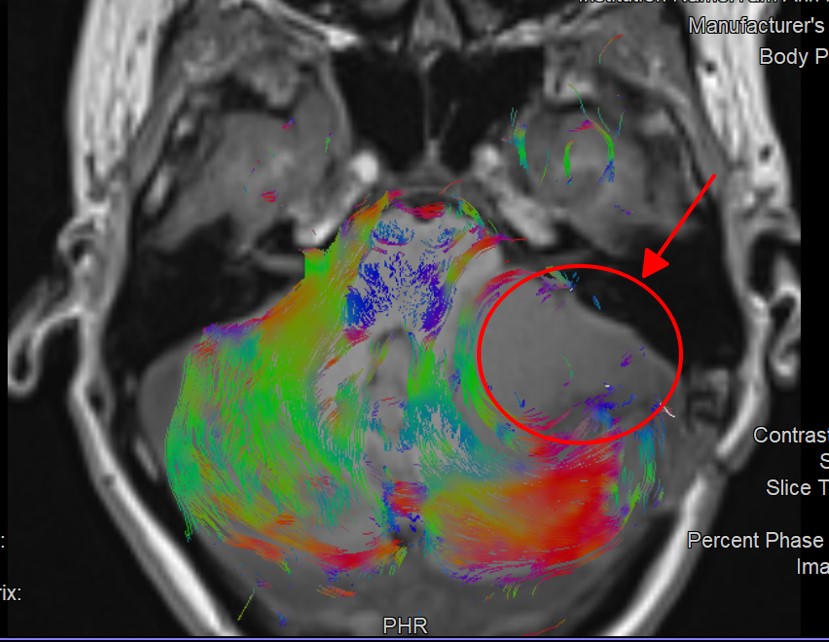

Kết quả chụp cộng hưởng từ MRI 3 Tesla kết hợp chụp các bó sợi thần kinh DTI cho thấy khối u vẫn còn, kích thước gần 5 cm. Khối u lớn, chèn ép tiểu não, cầu não và cuống tiểu não bên trái, đẩy cấu trúc thân não ra phía trước, gây thoát vị tiểu não trái xuống dưới. Các bó sợi thần kinh và đường giữa não cũng bị khối u đẩy lệch sang phải. Tình trạng này khiến chị Oanh đối diện với nguy cơ hôn mê, thoát vị não gây tụt não, chèn ép hành não, tử vong.